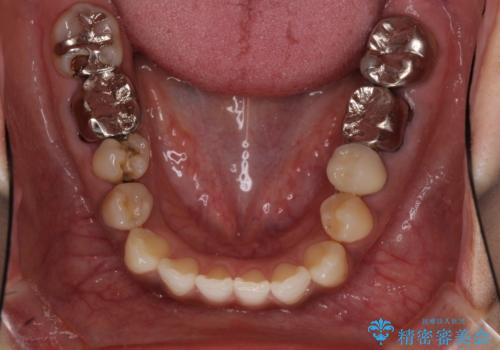

- 歯を削る量が少ないとの触れ込みで最近接着ブリッジを装着したものの、そのブリッジと歯の間に隙間ができているとのことで来院された患者様です。

歯の裏側を一層だけ削り、接着力に頼ったブリッジを装着してはみたものの、案の定咬む力に負けて、接着が剥がれてしまっていました。

歯を削る量は増えますが、より長い期間再治療なく使用していただくことを最優先に考え、フルカバレッジのオールセラミックブリッジにて補綴することとしました。

他にも、奥歯の銀歯の下にもむし歯が多くあり、痛みが生じていたため、根管治療などを行った上で、オールセラミッククラウンにて補綴治療することとしました。

前歯の裏側の接着面は、隙間ができていたことにより、汚れがたまるだけでなく、むし歯にもなっていました。